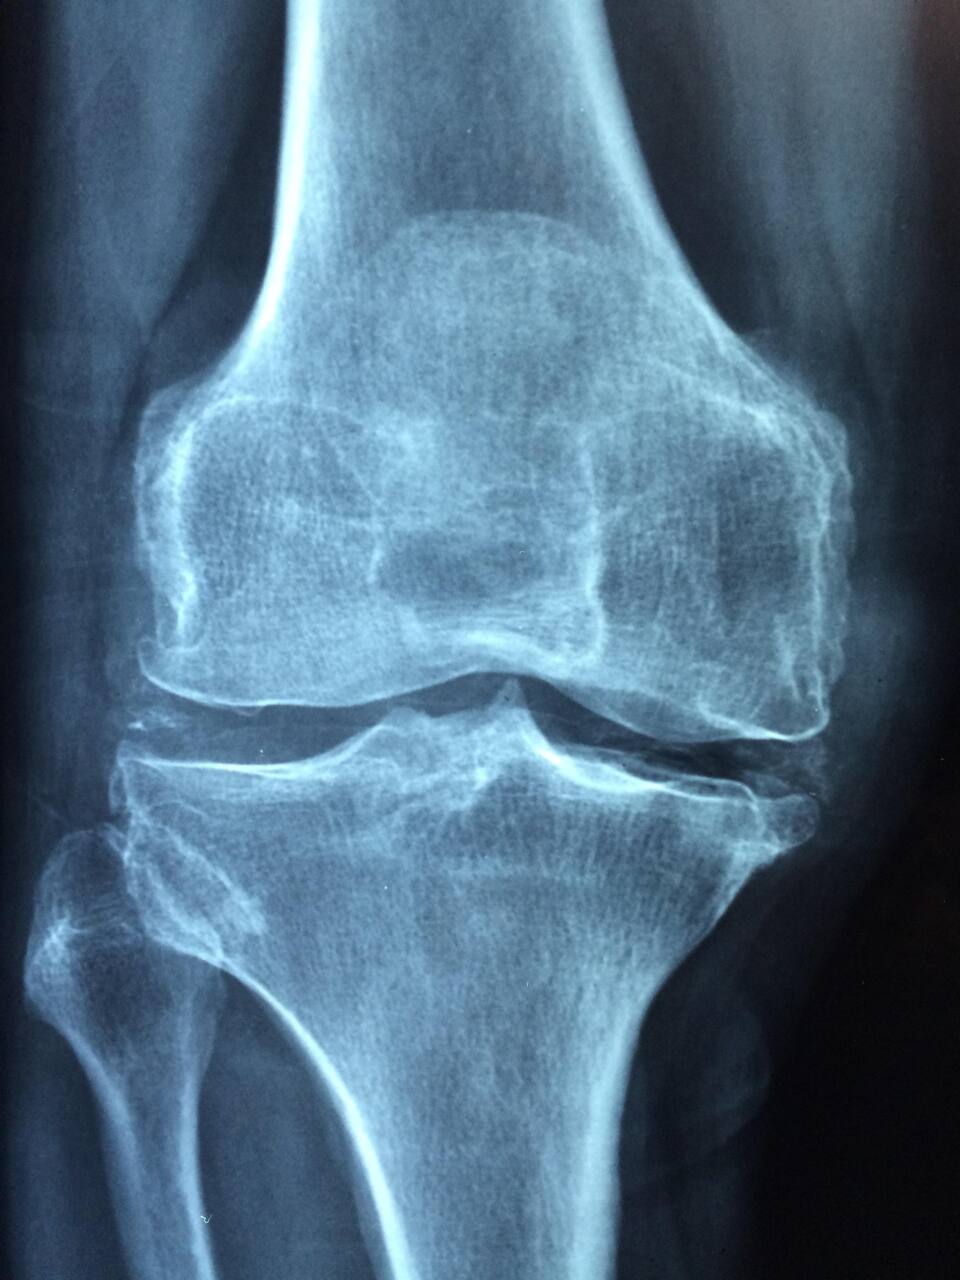

Symptomatologie et Diagnostic

Le tableau clinique dépasse la simple douleur. L’inflammation systémique peut provoquer :

-

Douleurs articulaires (mains, genoux, pieds) et raideurs matinales.

Œdèmes (gonflements) et sensation de chaleur locale.

Fatigue intense et inexpliquée.

Fièvre légère et perte d’appétit.

Le diagnostic précoce est la clé. Il repose sur un triptyque : examen clinique, imagerie médicale (radiographie, IRM) et bilan biologique (recherche d’anticorps spécifiques et marqueurs de l’inflammation).